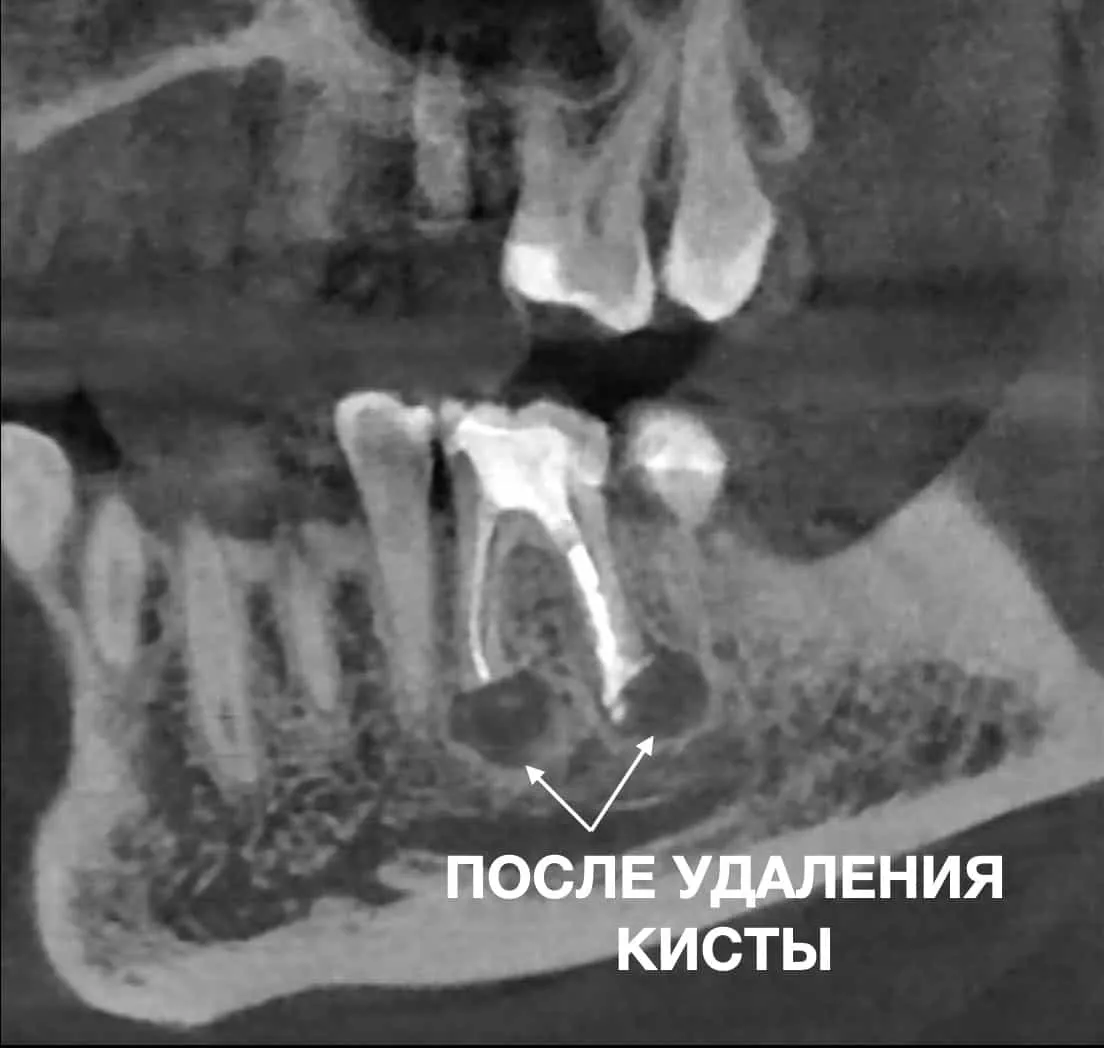

ПРИМЕР УСПЕШНОГО УДАЛЕНИЯ КИСТЫ ЗУБА В СТОМАТОЛОГИЧЕСКОМ ЦЕНТРЕ OLANKO DENTAL STUDIO

Апикальная (эндодонтическая) микрохирургия – это зубосберегающая операция, проводимая в участке верхушки корня зуба, с помощью хирургического доступа через кость, при этом удаляется инфицированная часть корня и зуб герметично пломбируется ретроградно, через хирургическую рану. Вся операция проходит с использованием дентального микроскопа и биосовместимых материалов.

Показаниями к данной операции являются те клинические случаи, при которых стандартное эндодонтическое лечение корневых каналов не дало положительного результата.

или в зубе есть блоки, которые не дают, качественно обработать корневые такие как ступени, сломанные инструменты, атипичная анатомия.

Также показаниями есть истинные кисты и инфекция вне корневого канала, на которые мы не можем повлиять консервативным эндодонтическим лечением.

Часто апикальная хирургия является единственным способом избежать удаления зуба.

Преимущества этого метода заключаются в том, что за довольно короткий промежуток времени проходит заживление раны и пациент быстро проходит период восстановления. Операция проводится в один визит, в течение 1-2 часов и вы выходите с тем же целым, сохраненным зубом.

Эндодонтическая микрохирургия радикально отличается от операции резекции верхушки корня, так как выполняется по значительно улучшенному протоколу, включающему в себя этапы проверки корня, очищение канала с обратной стороны и герметичного пломбирования.

Этот метод более сложен технически, но позволяет увеличить успех лечения с 50 до 90%.

Операция проводится методом навигационной хирургии с использованием хирургических шаблонов, что позволяет избежать ошибок, точно рассчитать место доступа и максимально сохранить здоровые ткани.